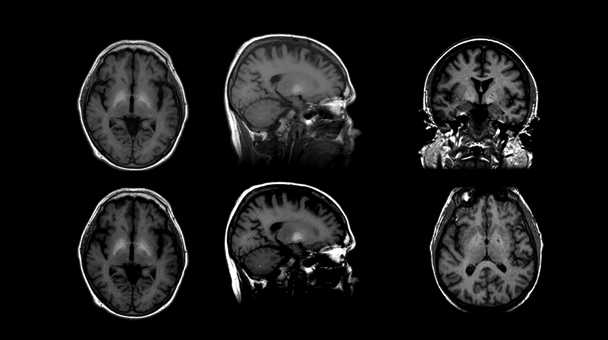

Structural MRI Findings in Uncomplicated Alcoholism

Relative to findings in WKS, research demonstrates mild volume deficits in the mammillary bodies (Shear et al. 1996; Sullivan et al. 1999), hippocampi, and thalami in uncomplicated alcoholics compared with healthy controls (De Bellis et al. 2005; Chanraud et al. 2007; Pitel et al. 2012; Sullivan 2003; van Holst et al. 2012). As shown in figure 5, these structures show a graded effect of volume deficits. That is, volume deficits are greatest in brains of subjects with KS (figure 5C) compared with brains of subjects with uncomplicated alcoholism (figure 5B) and brains unaffected by alcohol (figure 5A). Results suggest that mammillary-body damage is not prerequisite for the development of amnesia in alcoholism (Shear et al. 1996). MR findings also show hippocampal volume deficits in alcoholics compared with healthy controls (Agartz et al. 1999; Beresford et al. 2006; Kurth et al. 2004; Laakso et al. 2000; Sullivan et al. 1995; Wilhelm et al. 2008). Hippocampal volume deficits in alcoholism are influenced by age (Sullivan et al. 1995), even though age-related decline is difficult to detect in cross-sectional studies (Pfefferbaum et al. 2013; Raz et al. 2010; Sullivan et al. 2005b). Although deficits in hippocampal volume are not related to seizure incidence (Bleich et al. 2003; Sullivan et al. 1996), temporal-lobe white matter may be sensitive to alcohol-withdrawal seizures (Sullivan et al. 1996). Hippocampal volume shrinkage in alcoholism is attributed to loss of white matter and decreased axonal diameter (Harding et al. 1997). Glial cell loss (Korbo 1999) or reduced incorporation of newly formed neurons to the dentate gyrus (He et al. 2005; Nixon and Crews 2004), however, could also affect hippocampal volume in alcoholis

Other regions selectively affected in WE and KS include the orbitofrontal cortices (KS), periaqueductal gray matter, and tissue surrounding the third ventricle (WE). Reports suggest that propensity to relapse following sobriety is related to pronounced atrophy in bilateral orbitofrontal cortices (Beck et al. 2012; Cardenas et al. 2011; Durazzo et al. 2011; also see Rando et al. 2011). The third ventricle (i.e., enlargement) is sensitive to resumption of chronic alcohol consumption (Pfefferbaum et al. 2001; Sullivan et al. 2000b). There currently are no studies regarding periaqueductal gray-matter volume in uncomplicated alcoholics.

Key regions affected in HE include the globus pallidus and substantia nigra. Volume effects on these two structures have not been reported in uncomplicated alcoholics; however, in children with fetal alcohol syndrome, globus pallidus volume is reduced in size compared with unaffected children (Nardelli et al. 2011). In contrast, other basal ganglia nodes of reward circuitry have been described as affected in uncomplicated alcoholism (Durazzo et al. 2011; Makris et al. 2008): MRI studies have revealed smaller volumes of caudate (Boutte et al. 2012), putamen (Jernigan et al. 1991a), amygdala (Fein et al. 2006), and nucleus accumbens, especially in more recently sober alcoholics compared with healthy controls (Sullivan et al. 2005a). Given the role of the amygdala in emotional regulation and behavioral control (for review, see McBride 2002), however, researchers have speculated that premorbid amygdala volume deficits put individuals at heightened risk for developing AUD (Benegal et al. 2007; Clarke et al. 2008; Kamarajan et al. 2006).

CPM targets the pons and ACD affects the cerebellum. Total infratentorial volume (including pons, cerebellar hemispheres, vermis, fissures, cisterns, and fourth ventricle) is significantly smaller in uncomplicated alcoholics than control subjects. The volume of the pons (Chanraud et al. 2009b; Pfefferbaum et al. 2002b; Sullivan 2003) and cerebellum (i.e., hemispheres) (Boutte et al. 2012; Chanraud et al. 2007, 2009a; De Bellis et al. 2005; Sullivan et al. 2000a,c) is smaller in uncomplicated alcoholics than in normal controls. Alcoholism-related volume deficits are also prevalent in gray and white matter (Shear et al. 1996; Sullivan et al. 2003) of the cerebellar vermis (Antunez et al. 1998; Piguet et al. 2006; Sullivan et al. 2006b, 2010), predominately in anterior superior but not posterior inferior regions (Sullivan et al. 2000a) (see figure 6).

The frontal cortex is notably damaged in ARD. With respect to cortical regions in uncomplicated alcoholism, various methods have shown significant, widespread shrinkage of both cortical gray and white matter with corresponding increases in CSF-filled spaces (Cardenas et al. 2007; Jang et al. 2007; Jernigan et al. 1991a; Mechtcheriakov et al. 2007; Pfefferbaum 1992). In particular, older (older than age 50) but not younger adult alcoholics show disproportionate deficits in both gray- and white-matter cortical volume, especially in the frontal lobes, when volumes are statistically adjusted for brain tissue decline associated with normal aging (Cardenas et al. 2005, 2007; Pfefferbaum et al. 1997). This is the case even in comparisons made in groups selected on alcohol consumption, where older alcoholics have consumed equivalent amounts over their lifetime as younger alcoholics.

Thinning of the corpus callosum occurs in uncomplicated alcoholics and is more prominent in the anterior than posterior regions (Estruch et al. 1997; Pfefferbaum et al. 1996). As with WE and KS, evidence for MBD-like pathology in uncomplicated alcoholism raises the possibility that brain damage occurs on a continuum. The following section examines how brain structures and function respond when drinking stops.